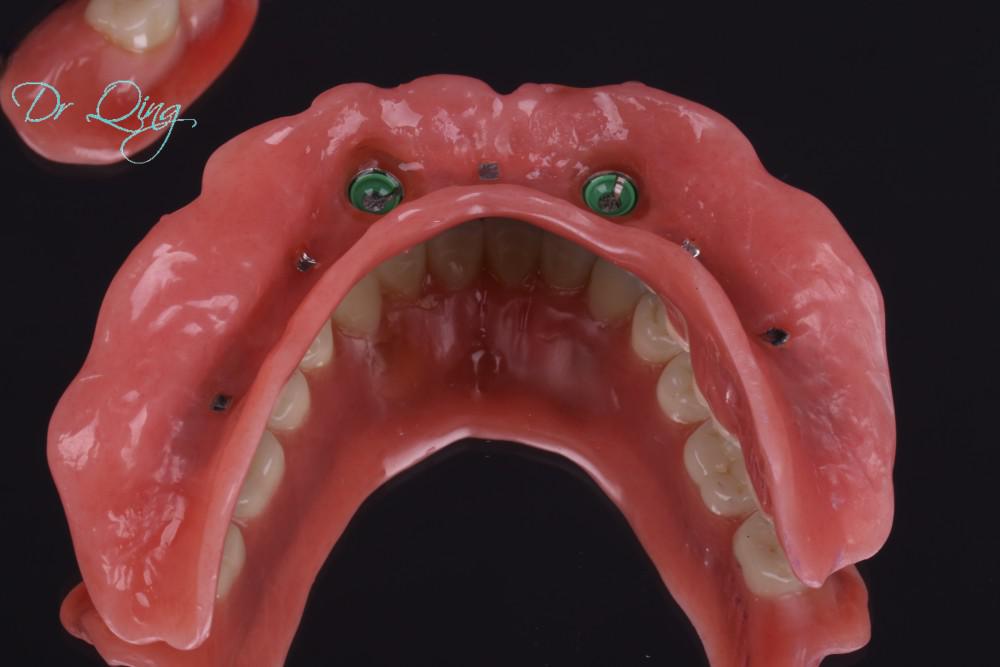

Overdenture in the maxilla is in a horseshoe shape and does not cover the whole palate; this way, it exposes more oral tissue for the patients to feel more comfortable and have more sensation to food.

Injection molding and layering staining techniques were used to fabricate high-quality denture with natural esthetics. Well designed oral reconstruction not only rehabilitates the oral function but also provides natural facial support and esthetics.